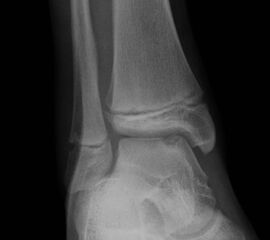

Röntgen

Die Standard Röntgendiagnostik des Sprunggelenks umfasst Bilder in anteriorposterioren (a.p.) und im seitlichen Strahlengang 6. Für die exakte Abbildung des Innenknöchels müssen beide Malleolen parallel zur Röntgenplatte zu liegen kommen. Je nach Torsion der Tibia macht dies eine Innenrotation des Fußes zwischen 10° und 30° erforderlich (Abb. 3).

Manchmal sind mediale Malleolarfrakturen nur in einer der Aufnahmen in ihrem Ausmaß erkennbar. Keine Rolle spielt die gehaltene Aufnahme beim Kind, insbesondere bei der akuten Verletzung. In seltenen Fällen hat dieses Verfahren bei Verdacht auf eine chronische Instabilität eine Berechtigung.